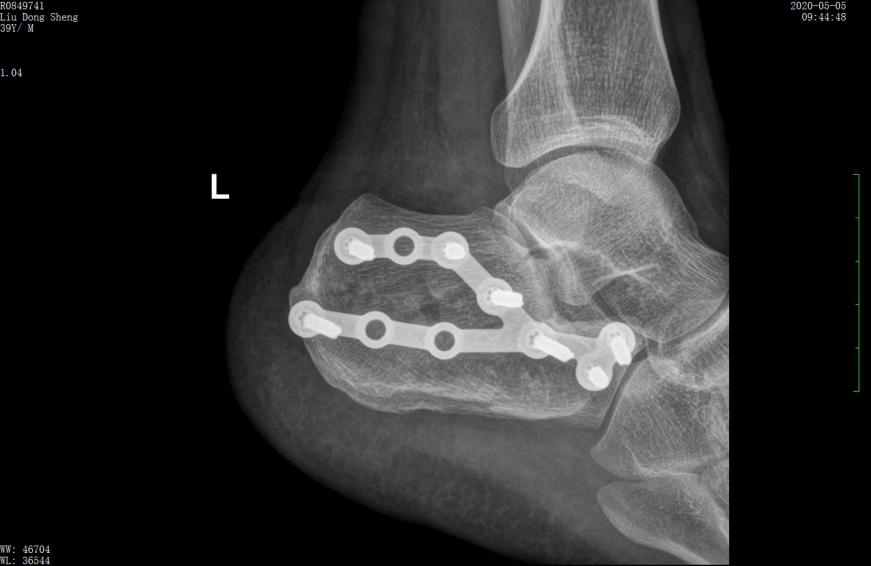

案例1影像

行微创手术治疗后,跟骨高度恢复,关节面平整